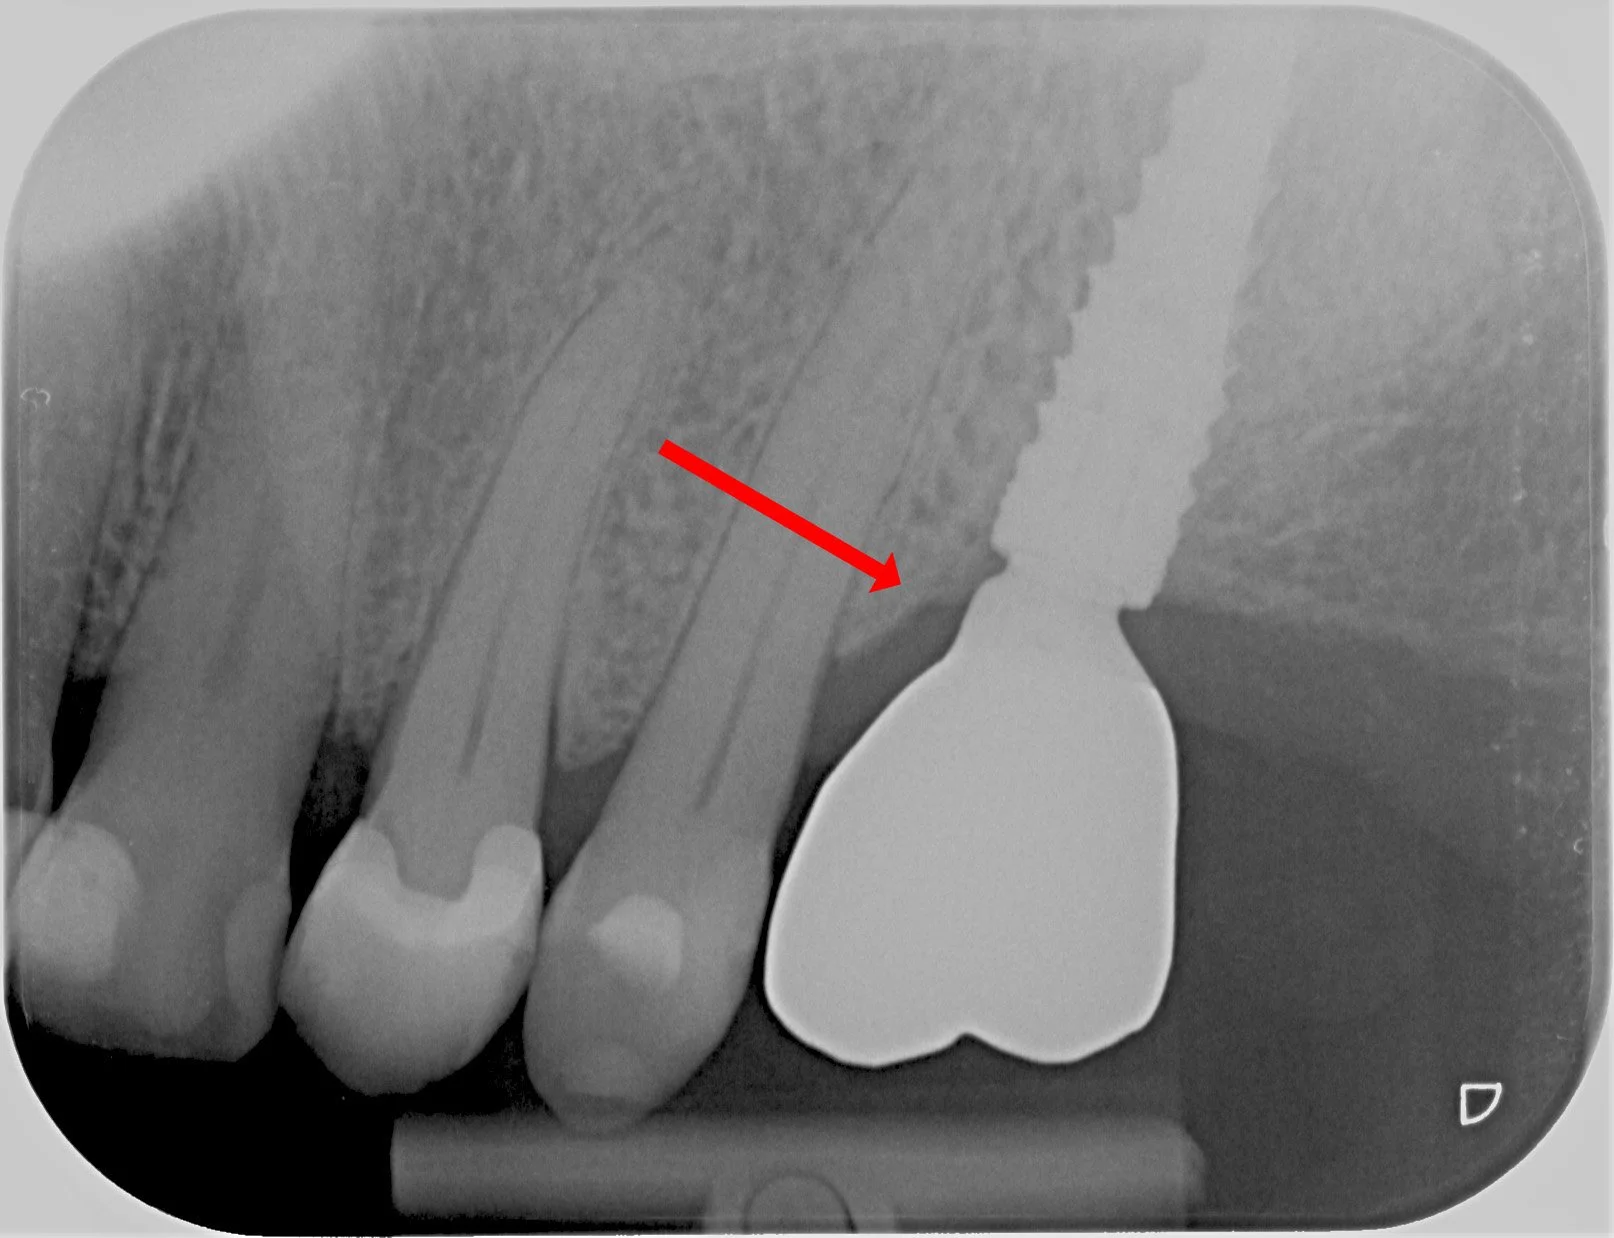

Jatke painaa distaalisesti ja aiheuttaa kipua potilaalle vuoden ajan

Kruunu irrotettu, jatke hiottu ja kiillotettu. Vaivat poistuneet.